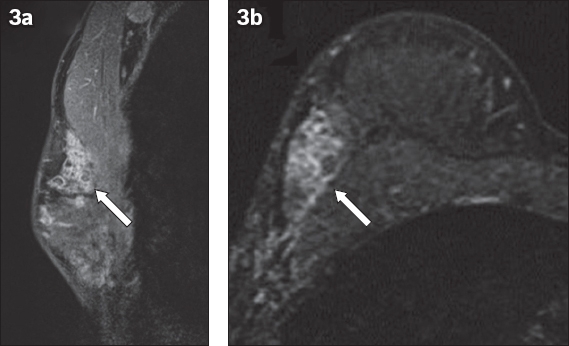

Selected (a) sagittal and (b) axial contrast-enhanced T1-W MR images of the right breast.

MR imaging is considered to be the most sensitive modality available for identifying DCIS, particularly high-grade DCIS. It is also a superior imaging technique for assessing the extent of disease, especially in the preoperative setting, which is useful in the assessment and planning of breast conservation surgery.(4,15,16) DCIS usually manifests as non-mass enhancement (NME)(17) and occasionally, as enhancing masses. The internal enhancement pattern that is commonly associated with DCIS is the clumped pattern,(15) while segmental and ductal types of distribution are also suspicious for DCIS. MR imaging kinetics is not useful in the assessment of NME, and the evaluation of morphology takes precedence in such lesions. Clustered ring enhancement is a recently recognised pattern of NME that is strongly associated with DCIS. The sign is now an accepted descriptor in the fifth edition of the BI-RADS (Breast Imaging Reporting and Data System) MR imaging lexicon. It is postulated that this sign represents periductal enhancement and contrast pooling in the ductal walls.(18) Tozaki et al first described this abnormal pattern of MR imaging enhancement in 2006, and it has been found to have a 77%–100% positive predictive value for malignancy, mostly related to DCIS.(18-20)

The clustered ring enhancement sign has also been found occasionally in invasive breast cancers and benign pathologies such as atypical ductal hyperplasia, papillomas and complex sclerosing lesions, which by themselves are associated with an elevated risk of breast cancer.(15,16) Indeed, DCIS can co-exist with these elevated-risk benign lesions, which makes adequate sampling essential. Yuen et al recommends that when the clustered ring enhancement sign is present on MR images, a biopsy with a thicker core needle (such as a vacuum-assisted biopsy needle) should be performed, as DCIS may only be present focally. In the event that the histological outcome from MR-guided percutaneous biopsy is benign, surgical resection should be considered to exclude malignancy.(21)